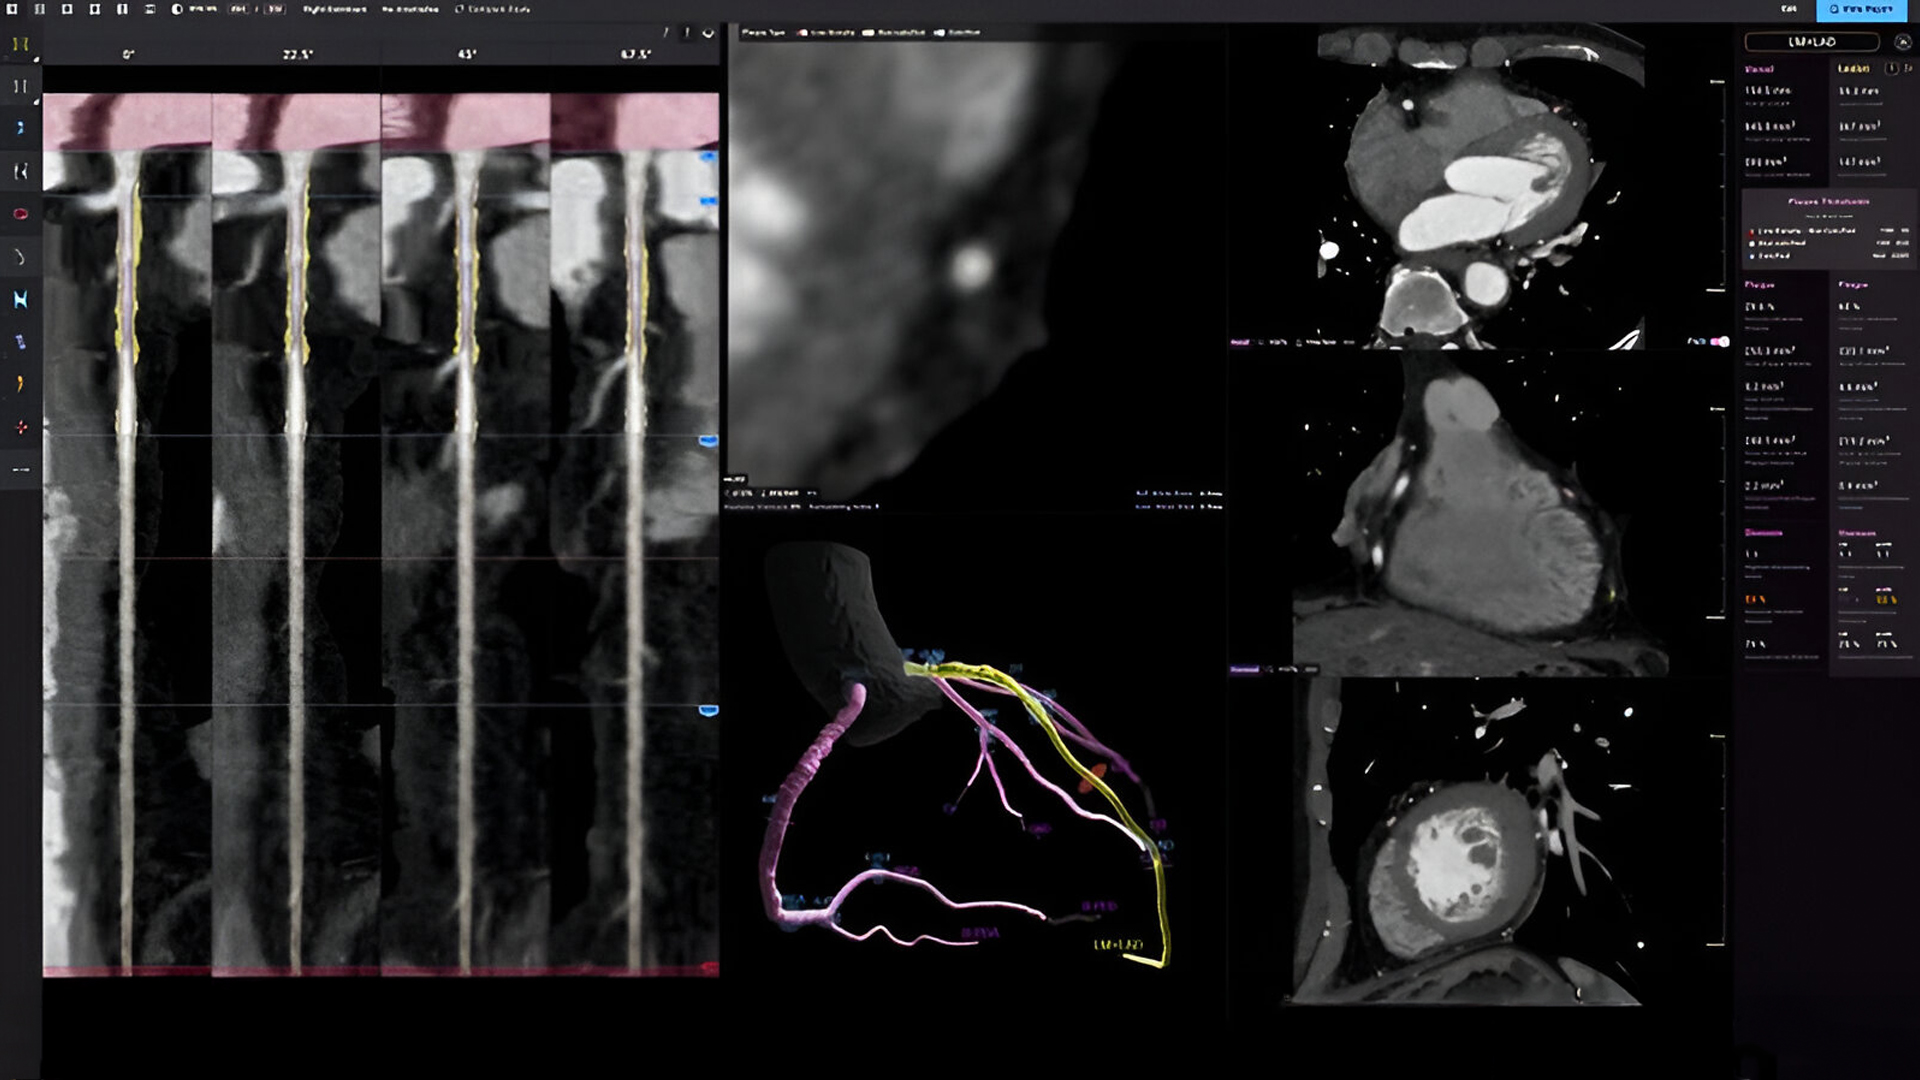

Imaging Highlights

- Embed AI tools into curricula: coronary plaque analysis, automated CMR, CT-FFR, PCI planning.